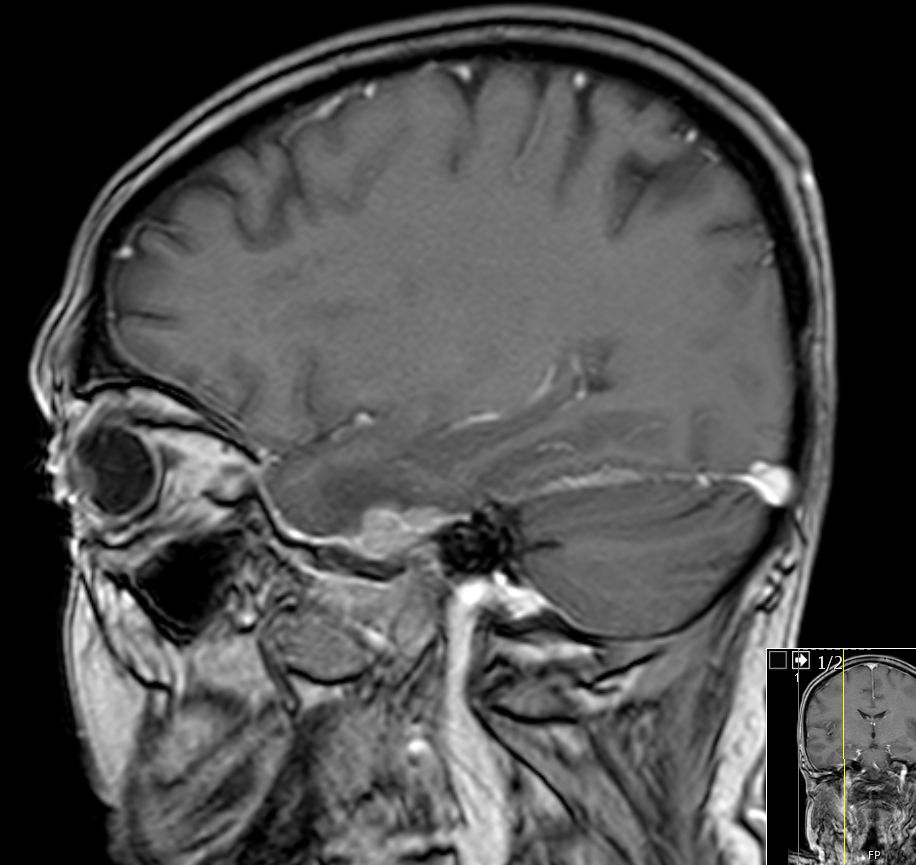

| Schädelbasis | 62-jährige Frau, bei der vor 2 Monaten ein Plattenepithelkarzinom der Zervix FIGO IIIB mit Radiochemotherapie behandelt wurde. Die Uterusgröße hatte von 13 auf 6 cm abgenommen. Jetzt Aufnahme mit der Diagnose Apoplex. | |||

An der Basalfläche des rechten Temporallappens KM - aufnehmende RF.![]() |

![]() | |||

![]() |

Unklare Doppelkontur der Meningen des Halsmarks.![]() |

Ödem des rechten Temporallappens.![]() | |||